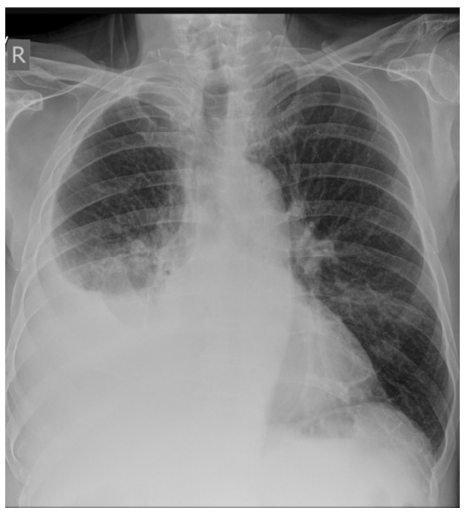

Paciente de 42 anos de idade, do sexo masculino, natural de Minas Gerais, foi trazido pelo irmão à Unidade de Pronto Atendimento devido a tosse secretiva, com início há 12 dias, associada a febre de 38 ºC, além de hiporexia e dor torácica. O paciente relata que já havia procurado a Unidade Básica de Saúde, ocasião em que lhe foi receitado o uso de macrolídeo por 5 dias, não havendo, contudo, melhora significativa dos sintomas.

Os exames laboratoriais do paciente realizados anteriormente apresentaram os seguintes resultados: hemoglobina 13 g/%; leucócitos totais 14.500/mm3; bastões de 5%; neutrófilos 75%; plaquetas 200.000/mm3; ureia 60 mg/dL.

A radiografia de tórax mostrou a seguinte imagem:

Além disso, foi realizada a toracentese para avaliação do líquido pleural, que mostrou: líquido pleural purulento; pH 6,8, DHL 2.000 U/L; proteínas 4,9 mg/dL; glicose 38 mg/dL; predomínio de neutrófilos.

II Aparelho respiratório: sons respiratórios abolidos em base direita; presença de algumas crepitações em região infraclavicular direita; macicez à percussão em base direita, com redução do frêmito toracovocal na mesma região.